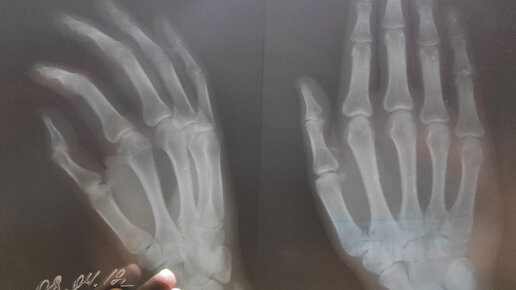

Приветствую на канале Просто о сложном. Поговорим про перелом. Как не навредить, но помочь человеку. Что нужно сделать, а от чего следует воздержаться. Обо всём этом в статье, читайте до конца, эта важная информация и может пригодиться каждому. Перелом — полное или частичное повреждение кости благодаря внешнему воздействию. Визуально (без врача) определить можно открытый перелом. При оказании первой помощи надо предполагать о самом серьезном варианте травмы. Поговорим немного о видах переломов...